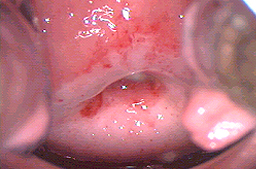

Desde hace muchos años se ha observado que si la piel infectada por Virus del Papiloma Humano (piel con lesiones o infectada) es destruida, se regenera con piel sana y el paciente puede eliminar la infección con una tasa de éxito variable dependiendo del tipo de aparato usado, y de la mejora que se obtenga en el sistema inmunológico de cada paciente.

Se han utilizado el electrocauterio y el asa diatérmica para la electrocauterización de las lesiones con una tasa real de éxito muy regular pues existe curación en el 93% de los pacientes, pero el 24% vuelven a presentar las lesiones en menos de 2 años, por lo que la tasa real de éxito es del 69%, y además tienen el inconveniente de ser muy dolorosos ya que no existe un control preciso de la profundidad con la que se destruye la piel por lo que penetran más de 1 mm, y afecta las terminaciones nerviosas, debido a esto los pacientes presentan dolor en los genitales externos, (las mujeres en vulva y los varones en pene) cuando practican deportes que ocasionan fricción en la zona o cuando tienen relaciones sexuales y esto puede durar hasta varios meses. Debido a las secuelas actualmente no se recomiendan dichos procedimientos para tratar los siguientes órganos: vagina, vulva, periné, región peri anal, ano y pene, con lesiones extensas.

La Crioterapia o Criocirugía ha sido utilizada para destrucción de la piel con lesiones del Virus del papiloma humano. Tiene el mismo inconveniente que los aparatos de electrocirugía ya que no mide la profundidad adecuadamente. La tasa de éxito inicial es del 83% con una recurrencia del 28% los primeros dos años. Debido al daño de las terminaciones nerviosas puede ocasionar, hipersensibilidad en los genitales.

Para destruir la piel también se ha utilizado el ácido triclorácetico ya que los dermatólogos lo utilizan para hacer peeling en la cara a un bajo costo, sin embargo los resultados no son adecuados ya que no se puede medir la profundidad de la piel quemada y ocasiona dolor de genitales por varios meses al igual que los aparatos antes mencionados es un producto económico con una tasa de éxito real del 40% pero con frecuencia deja secuelas transitorias con la hipersensibilidad severa que tarda meses en mejorar.

El mejor aparato actualmente que nos permite medir y regular con precisión la profundidad de la piel que se desea destruir o la piel infectada es el LASER CO2, cuando es utilizado por un colposcopista experto,(el cual se adquiere cuando un ginecólogo realiza el entrenamiento en colposcopía por seis meses en una Clínica de Displasias), y capacitación técnica en el manejo del laser CO2. Ya que los tratamientos deben tener una profundidad menor a 1 mm (800 micras máximo) para que no afecten las terminaciones nerviosas y por lo tanto no dejen secuelas. Su aplicación se hace bajo anestesia local por lo que es indolora. Su tasa de éxito es alta, del 89% con recaídas del 8% durante los primeros 2 años. Por lo que actualmente es el mejor tratamiento para el Virus del Papiloma Humano y las lesiones precancerosas de genitales externos, vagina y las lesiones extensas en cérvix, (extensión de lesiones a fondos de saco vaginales). Aclarando que la tasa de éxito depende de la capacitación del médico que lo aplica, existen estudios en que la tasa de éxito es incluso del 50% debido a la mala técnica utilizada.